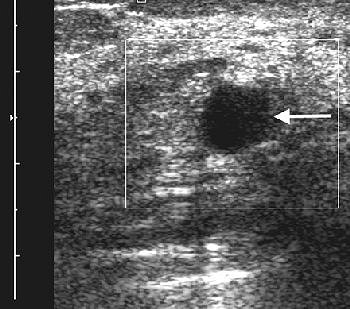

![]() |

| A 47-year-old woman with palpable mass in left breast considered indeterminate and likely complicated cyst on conventional B-mode sonography. Sonogram of left breast shows 1-cm complicated cyst (arrow) with low-level internal echoes. |